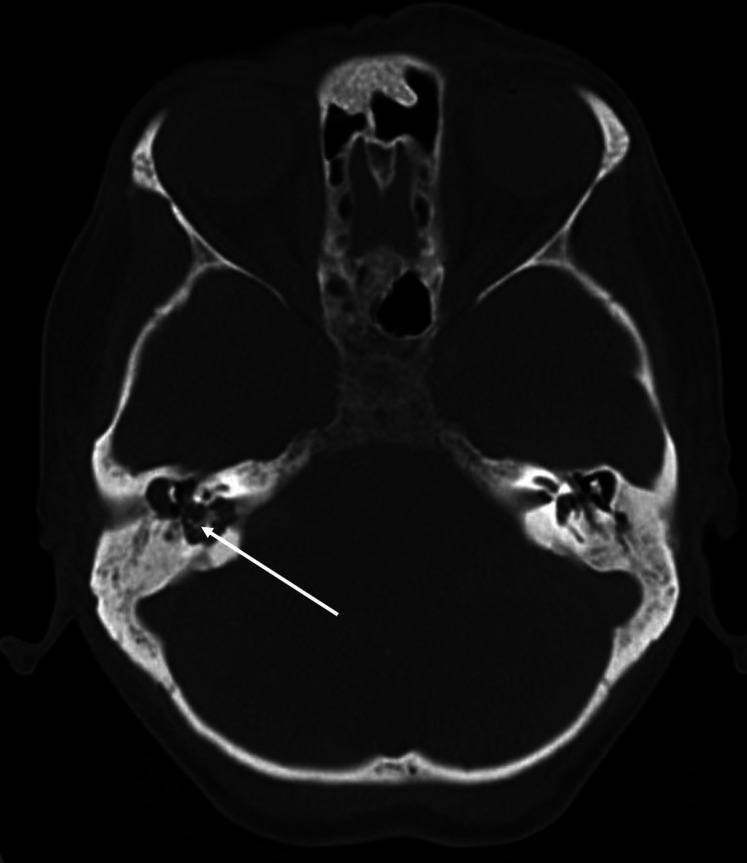

据报道,小脑脓肿是慢性化脓性中耳炎(CSOM)的一种并发症,有时会危及生命。小脑脓肿通常是由慢性化脓性中耳炎通过盆骨的骨质侵蚀或乙状窦的血栓性静脉炎直接传播引起的。然而,通过颅神经的解剖桥将感染从隐骨传播到小脑的另一种途径以前可能从未被描述过。一名患有 CSOM 和胆脂瘤的 63 岁女性患者出现共济失调和右侧面瘫。计算机断层扫描(CT)显示右侧耻骨骨质侵蚀,提示中耳感染。对比后磁共振成像显示,肿胀的第 7/8 神经复合物增强,提示神经炎,右侧岩骨有胆脂瘤。磁共振成像还显示同侧小脑脚有环形强化病变,提示脑脓肿。紧急进行了手术治疗,并抽出了脓液。随后,耳鼻喉科团队还为她进行了乳突切除术和胆脂瘤切除术,最终她的病情有所好转。本病例说明,CSOM 可通过颅神经的解剖桥传播感染而导致小脑脓肿,而不会直接从颞骨或鼻窦血栓性静脉炎侵入。

Cerebellar abscess is a reported complication of chronic suppurative otitis media (CSOM) and is life threatening at times. It usually develops by direct spread of CSOM through the bony erosion in the petrous bone or by thrombophlebitis of the sigmoid sinus. However, an alternative pathway of infection transmission from the petrous bone to the cerebellum through the anatomical bridge of the cranial nerves has possibly not been described before. A 63-year-old female patient with CSOM and cholesteatoma developed ataxia and right facial palsy. Computed tomography (CT) showed bone erosion of the right petrous bone suggesting middle ear infection. Post-contrast MRI revealed an enhancement of swollen 7th/8th nerve complex, suggesting neuritis, and cholesteatoma in the right petrous bone. It also showed ring enhancing lesion in the cerebellar peduncle of the same side suggesting brain abscess. Surgical intervention was performed emergently and pus aspirated. She also underwent mastoidectomy and removal of cholesteatoma later by the otolaryngology team and finally got better. This case illustrates that CSOM can cause cerebellar abscess by spreading infection via anatomical bridge of the cranial nerves without direct invasion from the temporal bone or thrombophlebitis of sinus.